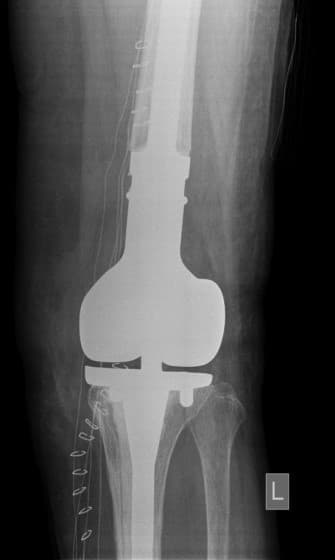

Сэргээн засах мэс засал: Зүүн дунд чөмөг-өвдөгний үе сэргээх тусгай протез суулгах мэс засал.

Үе дайрсан ясны анхдагч хавдар, ясны дутмагшлын үед хийгдэх мэс засалimg17Үе дайрсан ясны анхдагч хавдар, ясны дутмагшлын үед хийгдэх мэс засалimg18

Зураг 1. Сэргээн засах мэс заслын өмнөх рентген зураг. Эгц урд, хажуугаас авсан байдал.

Зураг 3. Мэс заслын дараах рентген зураг. Эгц урд, хажуугаас авсан байдал

Энэ тохиолдолд үений шөрмөсөн холбоос хэвийн хадгалагдаж үлдсэн байсан. Хиймэл үе - ястай тогтвортой сайн бэхлэгдэх нөхцлийг хангах чөмөгт гол руу орсон уртасгагч – extension stem-тэй хиймэл үе.